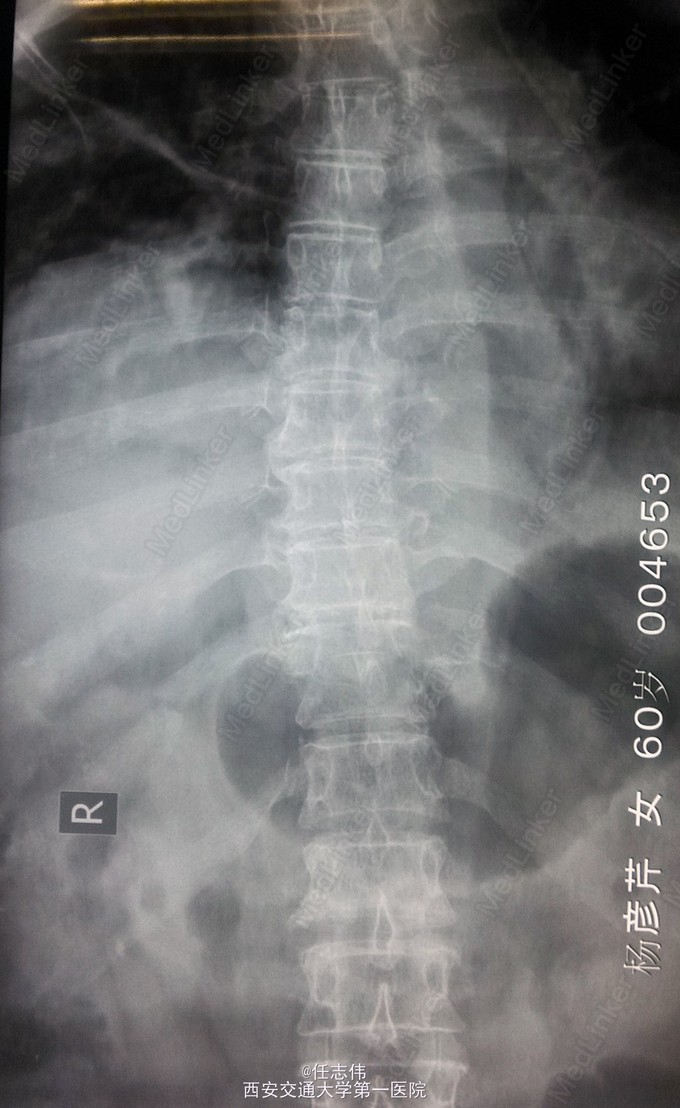

患者女性,60岁,车祸伤致双下肢感觉活动不能8h入院。 8小时前坐农用车时,被横杆撞倒腰部,摔下后感觉胸背部疼痛,双下肢活动不能,伴有短暂昏迷病史。遂来我院就诊。

左侧胸壁广泛压痛,呼吸急促。专科查体:胸背部广泛压痛,自腹股沟平面以下感觉、运动消失,腹壁反射消失,肛门反射消失,巴氏征阴性。双上肢感觉运动正常,骨盆分离挤压试验阴性。

诊断:1.胸11椎体骨折伴截瘫(Frankel A级)2.闭合性胸部损伤,肺挫伤,多发肋骨骨折,双侧胸腔积液 处理:1.急诊入院告病危,心电血氧监护;2.予以甲强龙冲击治疗;3.次日复查胸部CT,查看肺部损伤情况及胸腔积液,后予以右侧放置闭式引流。患者氧合不稳定,2日后复查胸片胸腔积液减少,予以行后路减压内固定融合术。 手术:术中见局部软组织损伤严重,胸11-12棘上、棘间韧带断裂,胸10、11、12双侧关节突有骨折移位,胸11椎板骨折,胸11左侧不能置入椎弓根螺钉,遂行单纯固定。脊髓局部挫伤明显,并有硬膜破损,予以处理。